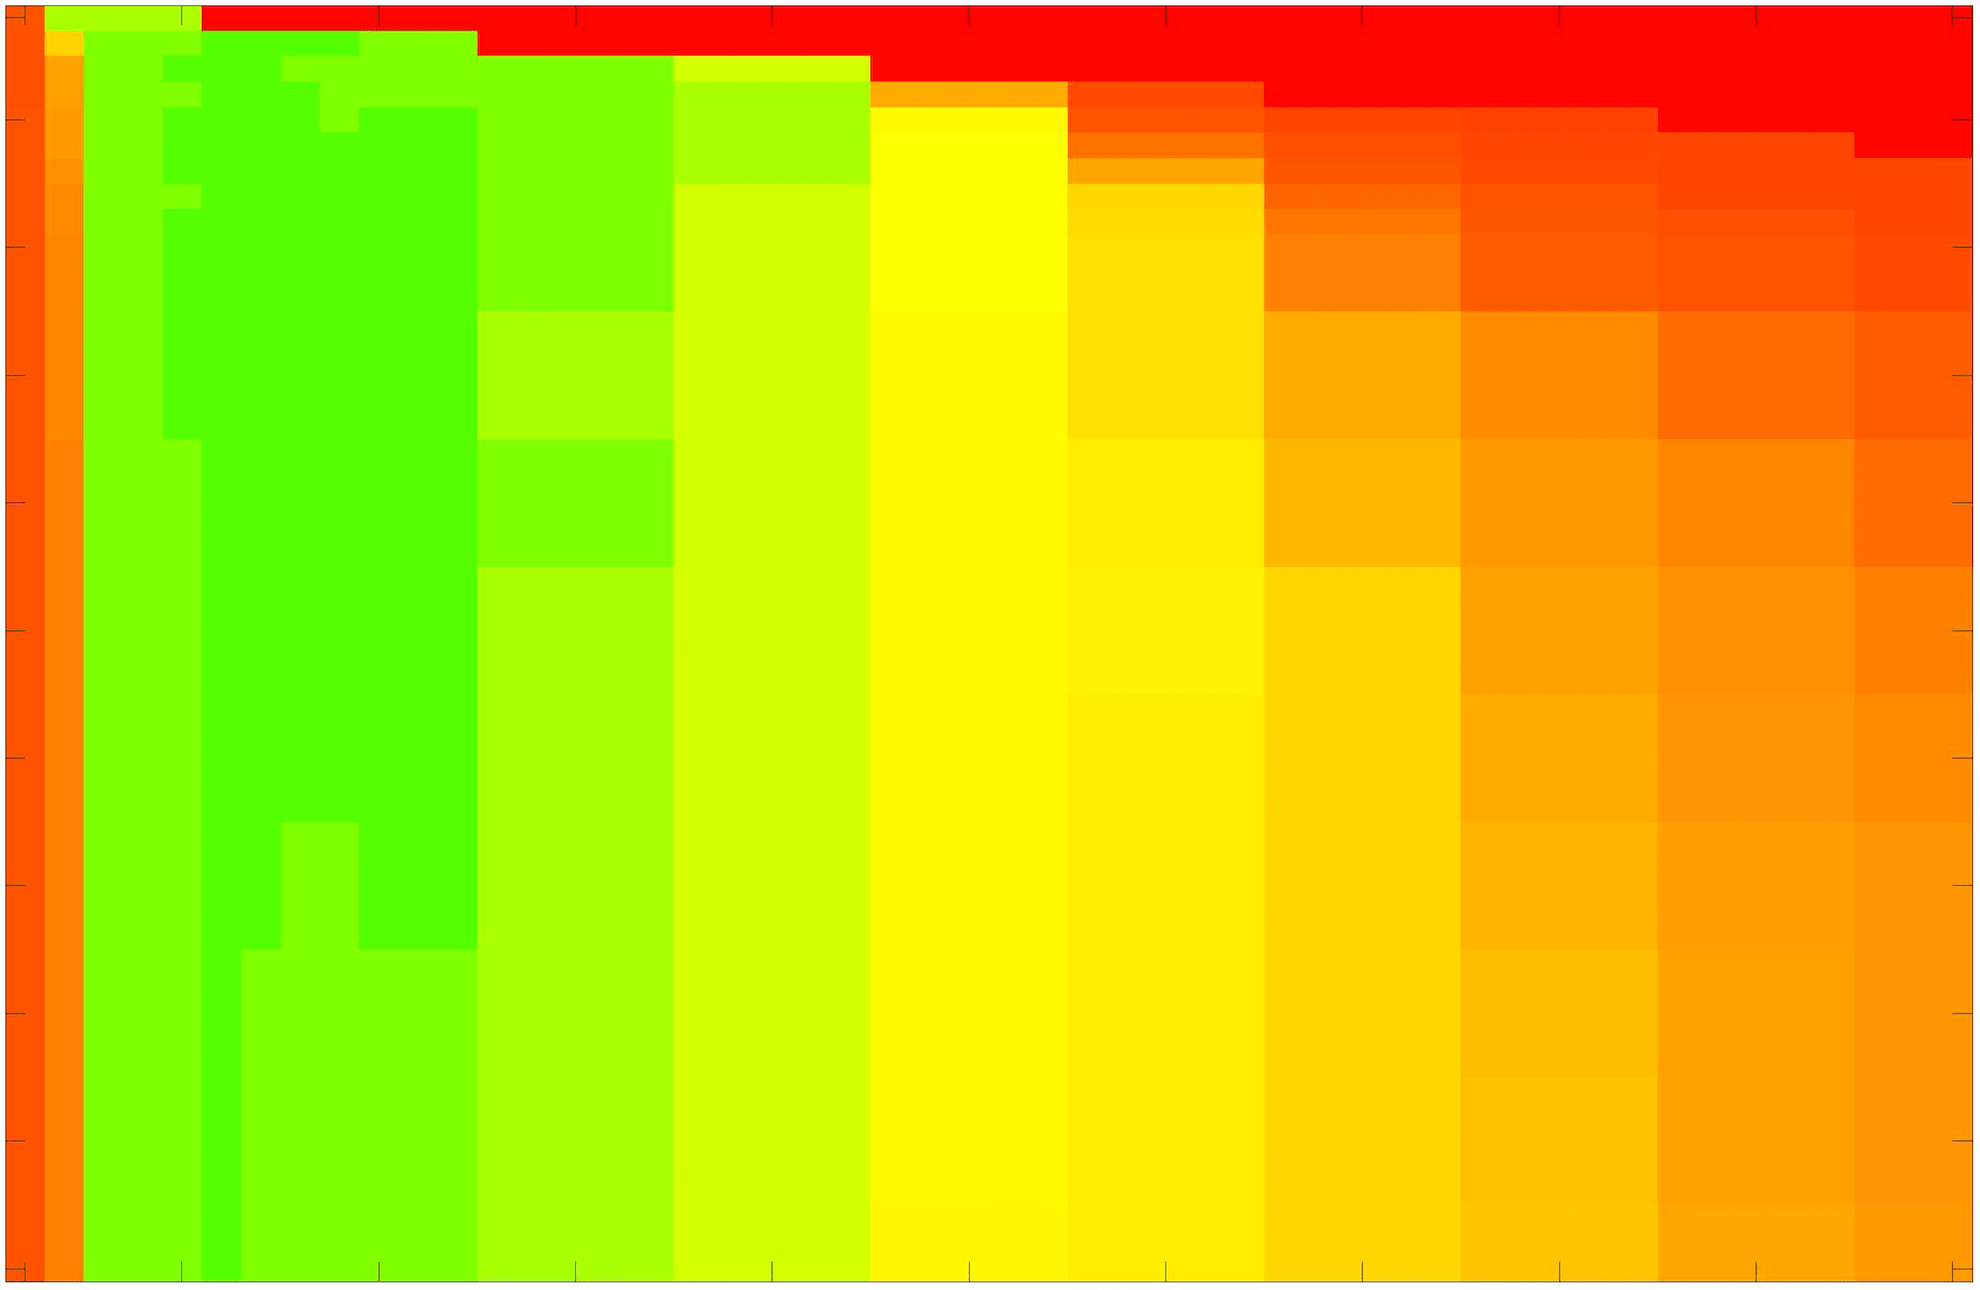

where refers to the number of points in the enclosed region. This takes values in the range , with higher TC values indicating a more accurate segmentation. In the following we will represent accuracy visually from red () to green (), with the intermediate scaling of colours used shown in Fig. 8. This will be particularly relevant in §7.2.

The TC values for the parameter sets are presented as heatmaps in Figs. 11–13. A heatmap is a convenient way to display accuracy results for hundreds of tests concisely. In Fig. 9 we give an example heatmap with the same axes used for those in Figs. 11–13. For each of the combinations of parameter values we give the TC value of the segmentation result and represent it by the appropriate colour. The corresponding colour scale is shown in Fig. 8. Qualitatively, the more green areas of the heatmap the more accurate the model is for a wider set of parameters. Example results for Test Image 5 when varying (with ) for the proposed model are given in Fig. 10. Here it can be seen what each accuracy result corresponds to visually.

Note. The axes have been removed from the heatmaps in Figs. 11–13 for presentational clarity. However, to be explicit, the axes used in all heatmaps are the same as those in Fig. 9.

Synthetic Images. These results are presented in Fig. 11. For Test Images 1–2 we see poor parameter robustness from all competing models, except for GAV which performs reasonably well. However, the proposed model has minimal parameter sensitivity for these images, with good results achieved for almost every combination of values tested. For Test Image 3 all models have a reasonable parameter range (except for RSF), however the proposed model gives better quality results for a wider parameter range. The other models achieve reasonable results here as the foreground intensity of the ground truth is greater than the background , whereas for Test Images 1–2 they are equal . These results highlight the key advantage of the proposed model.

Real Images. In Fig 12 we present results for Test Images 4–6. Here, the proposed model performs in a similar way to its competitors because these images are more typical selective segmentation problems in the sense that there is a clear distinction between the foreground and background intensities. In particular, the values in each case are: Test Image 4 , Test Image 5 , and Test Image 6 . It can be seen that the proposed model is competitive compared to previous approaches. The performance is quite poor for Test Image 5, but is arguably still the best for this challenging case. In Fig. 13 we present results for Test Images 7–9. Here the proposed model outperforms previous approaches significantly for each image. This is mainly due to the type of image considered. Specifically, the true intensities are: Test Image 7 , Test Image 8 , and Test Image 9 . The proposed model is capable of achieving results where , with other models failing completely in these cases.